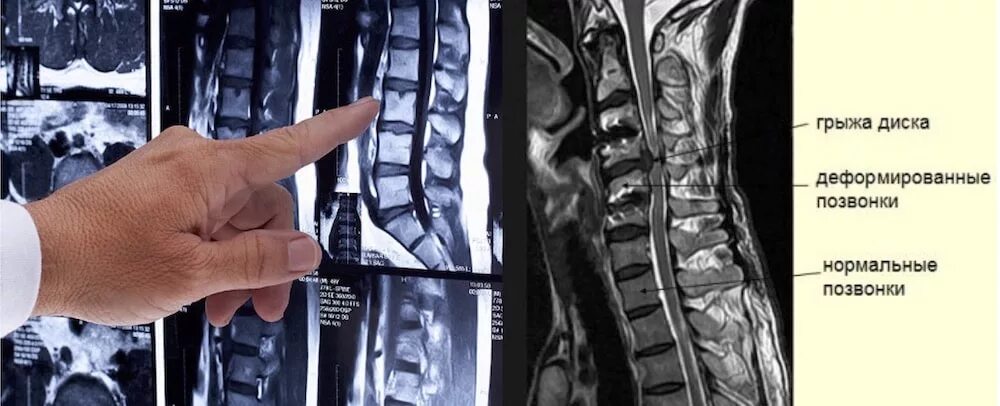

Перед мрт позвоночника можно кушать